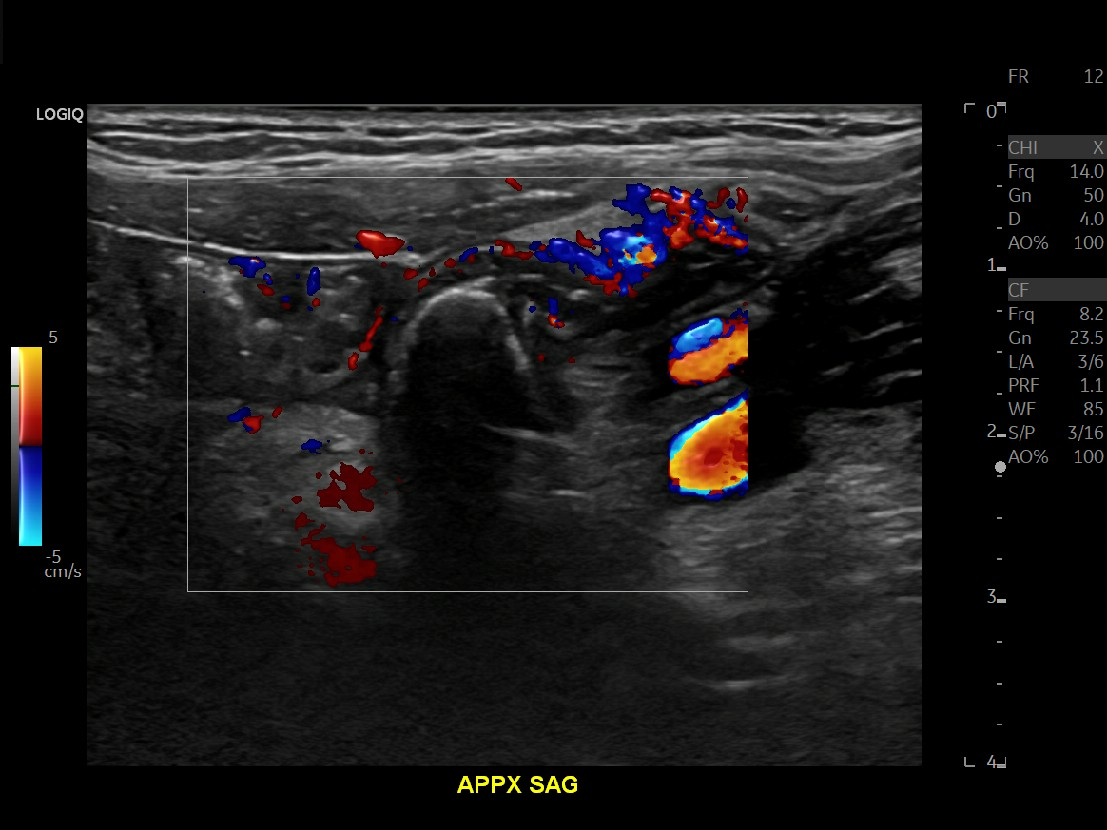

Appendicitis 14

Large appendicitis with appendicolith, hyperemia, fat standing and lympadenitis.